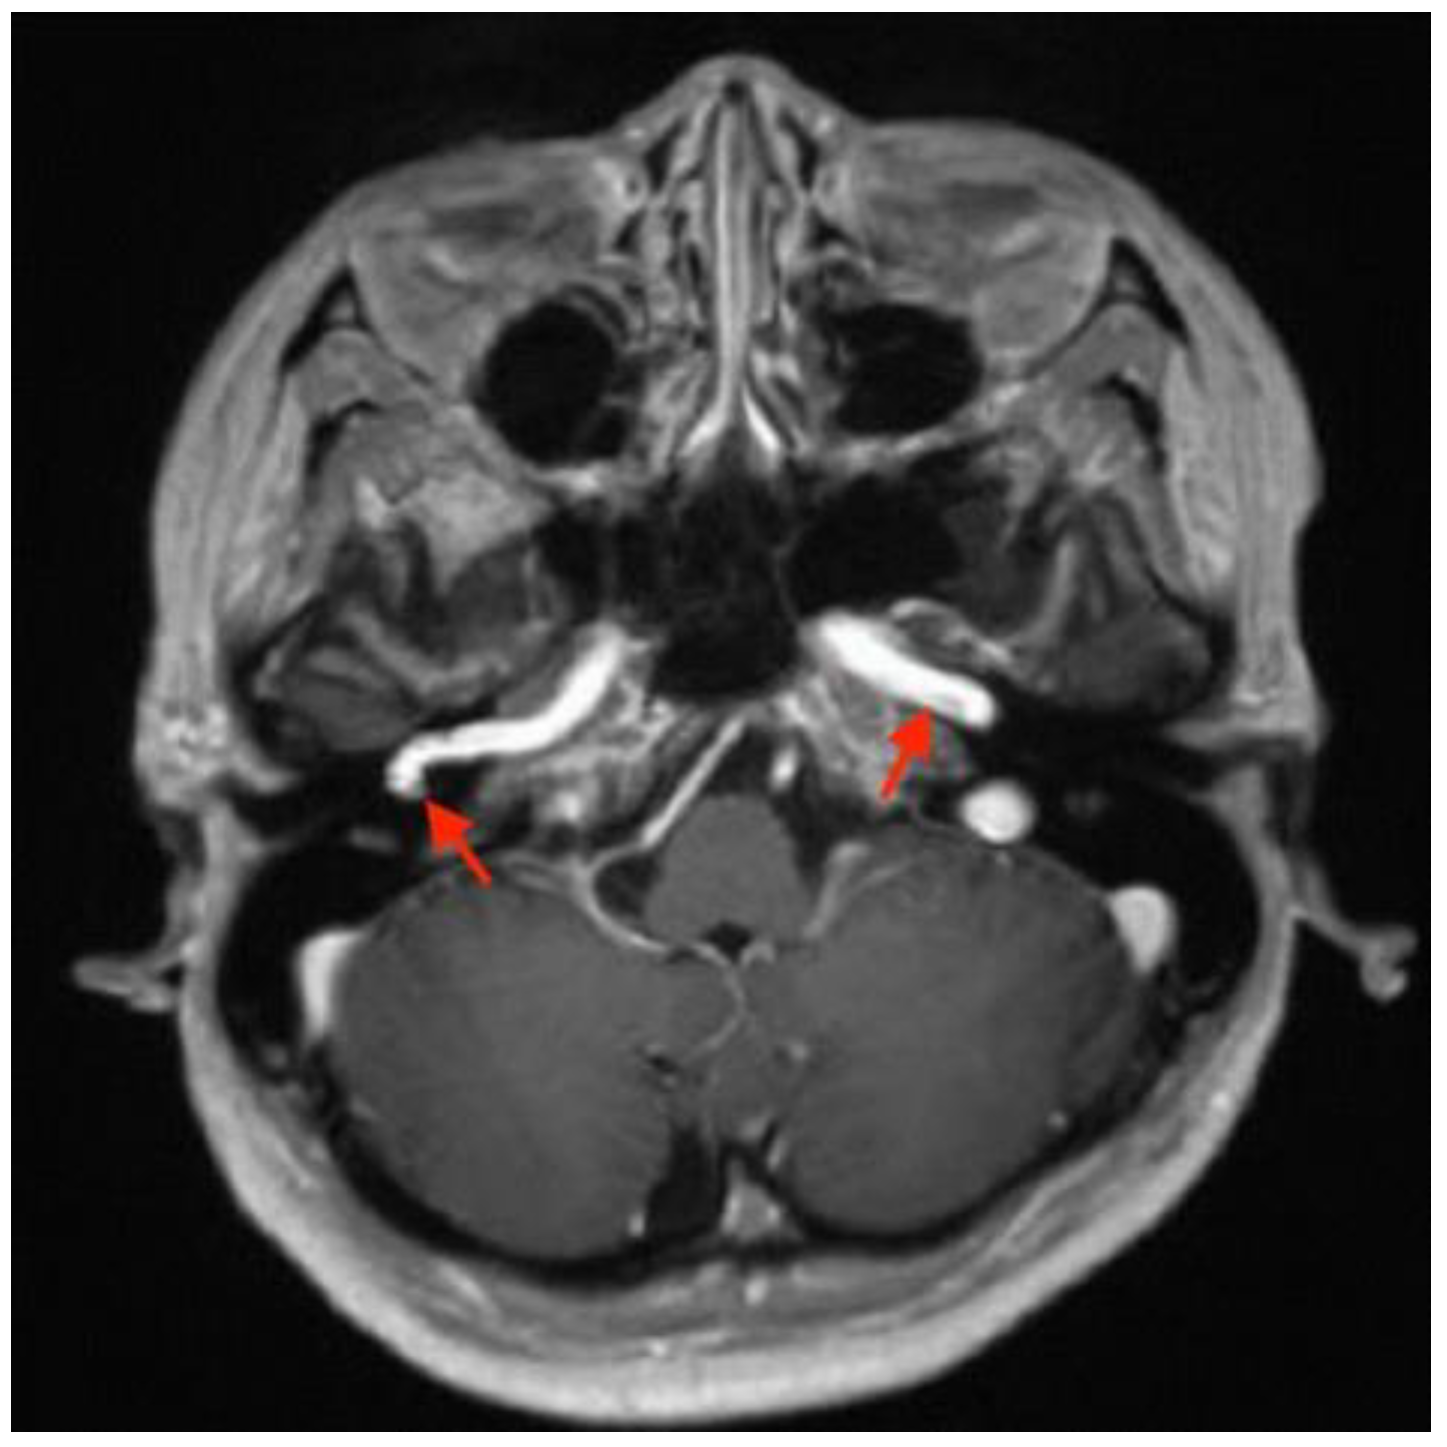

Imaging studies were subsequently performed to assess the etiology of the mass in her tympanic cavity. Unenhanced high-resolution computed tomography (HRCT) of the temporal bone revealed lateral bulging of the right ICA to the inferomedial portion of the right tympanic cavity without a bony covering, an enlarged right inferior tympanic canaliculus, and a hypoplastic right carotid canal (Figure 3). However, no other obvious abnormalities were noted in the right external auditory canal (EAC), middle ear, inner ear, and internal auditory canal (IAC). The EAC was patent and normal in configuration. The ossicles were normal in structure. The tympanic cavity and mastoid cells were clear. The configuration of the cochlea, vestibule, and semicircular canals was normal. No obvious abnormalities were noted in the IAC, petrosal apex, and cerebellopontine angle (Figure 4). Gadolinium-enhanced magnetic resonance imaging (MRI) of the head also revealed lateral bulging in the right ICA to the right tympanic cavity (Figure 5). Serial imaging studies indicated a diagnosis of right aICA.

Figure 5.

Gadolinium-enhanced magnetic resonance image revealing a normal left internal carotid artery (ICA) (arrow on the patient’s left) and lateral bulging of the right ICA to the right of the tympanic cavity (arrow on the patient’s right) in the axial view.